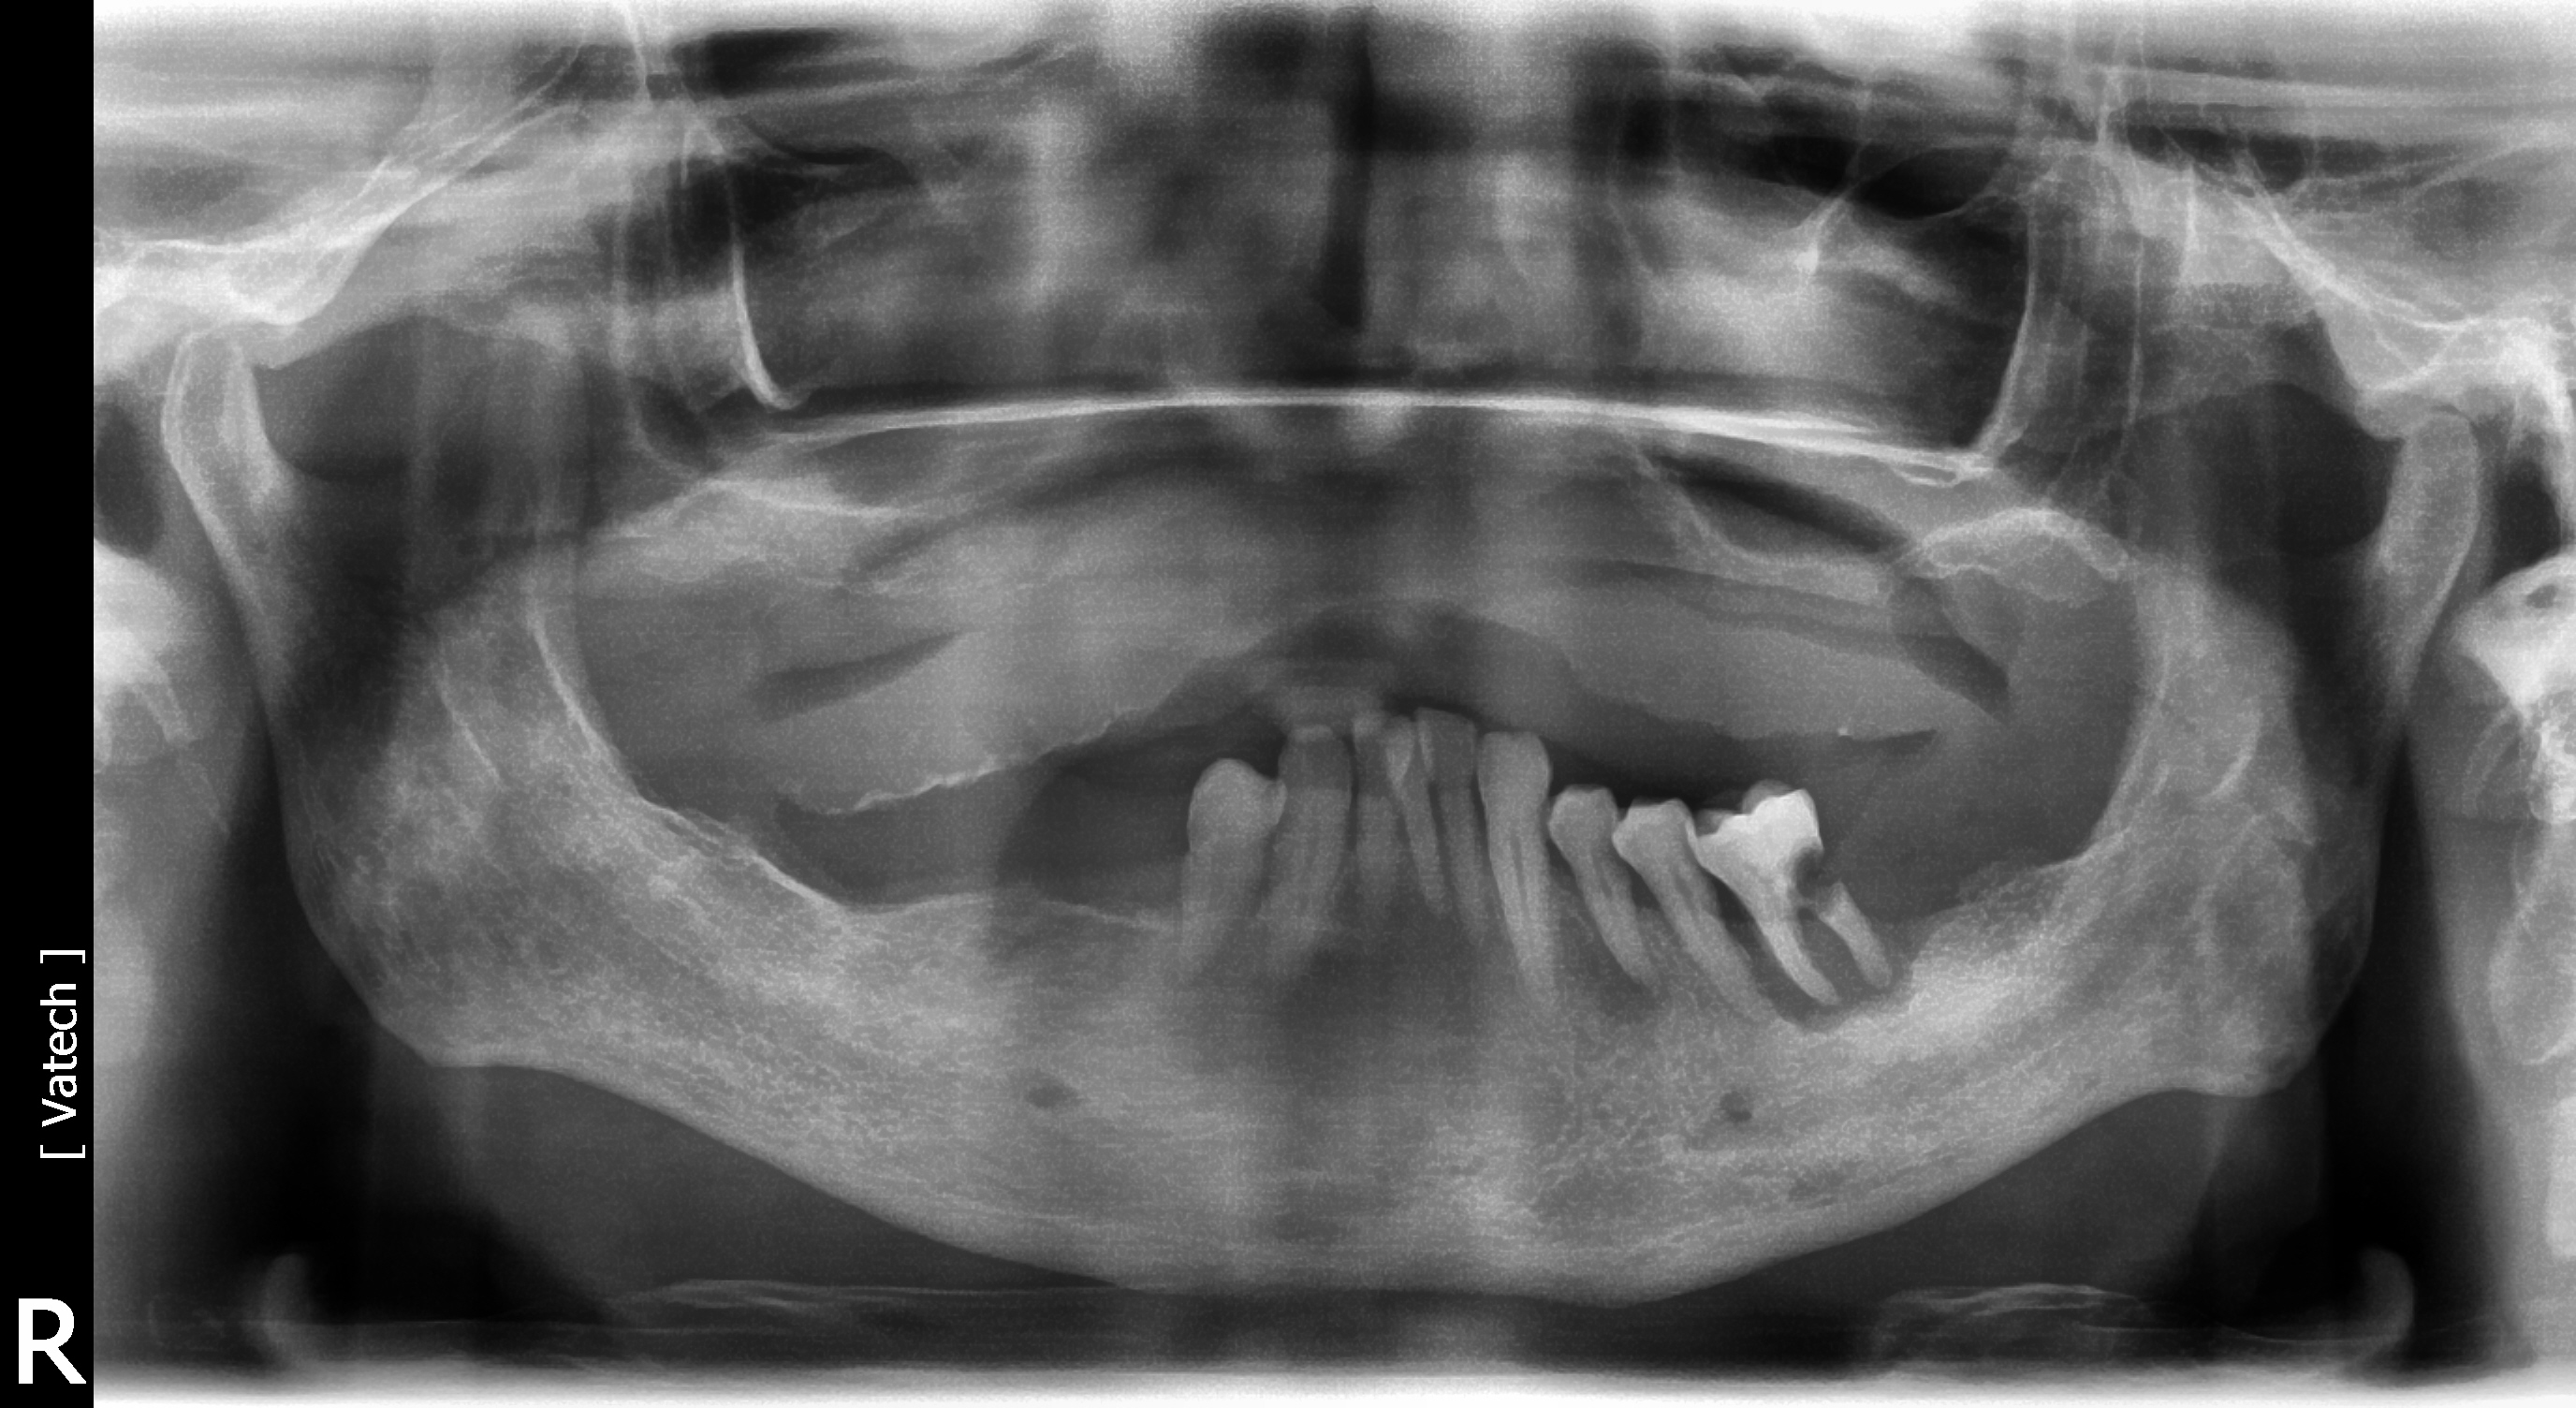

A 75-year-old man presented with a failing dentition (Figure 2 and Figure 3). Upon evaluation, the patient indicated that he desired a new maxillary complete denture and a mandibular overdenture, and the clinician discussed with him the possible option of two or four implants for his mandibular arch. However, upon further analysis, the patient was found to have extensive periapical lesions in the mandibular left first molar region. Additionally, the patient expressed that, owing to his advanced age, he was concerned about surgical complexity and the cost of reconstruction with four implants, and stated a preference for a simpler and more expedited treatment.

Fig 3. Radiograph showing extensive periodontal disease. After being presented with the option to have two or four implants, the patient chose to have two implants. Because he wanted the option to have additional implants in the future, the implants were placed in regions that would permit placement of additional implants.

Figure 3